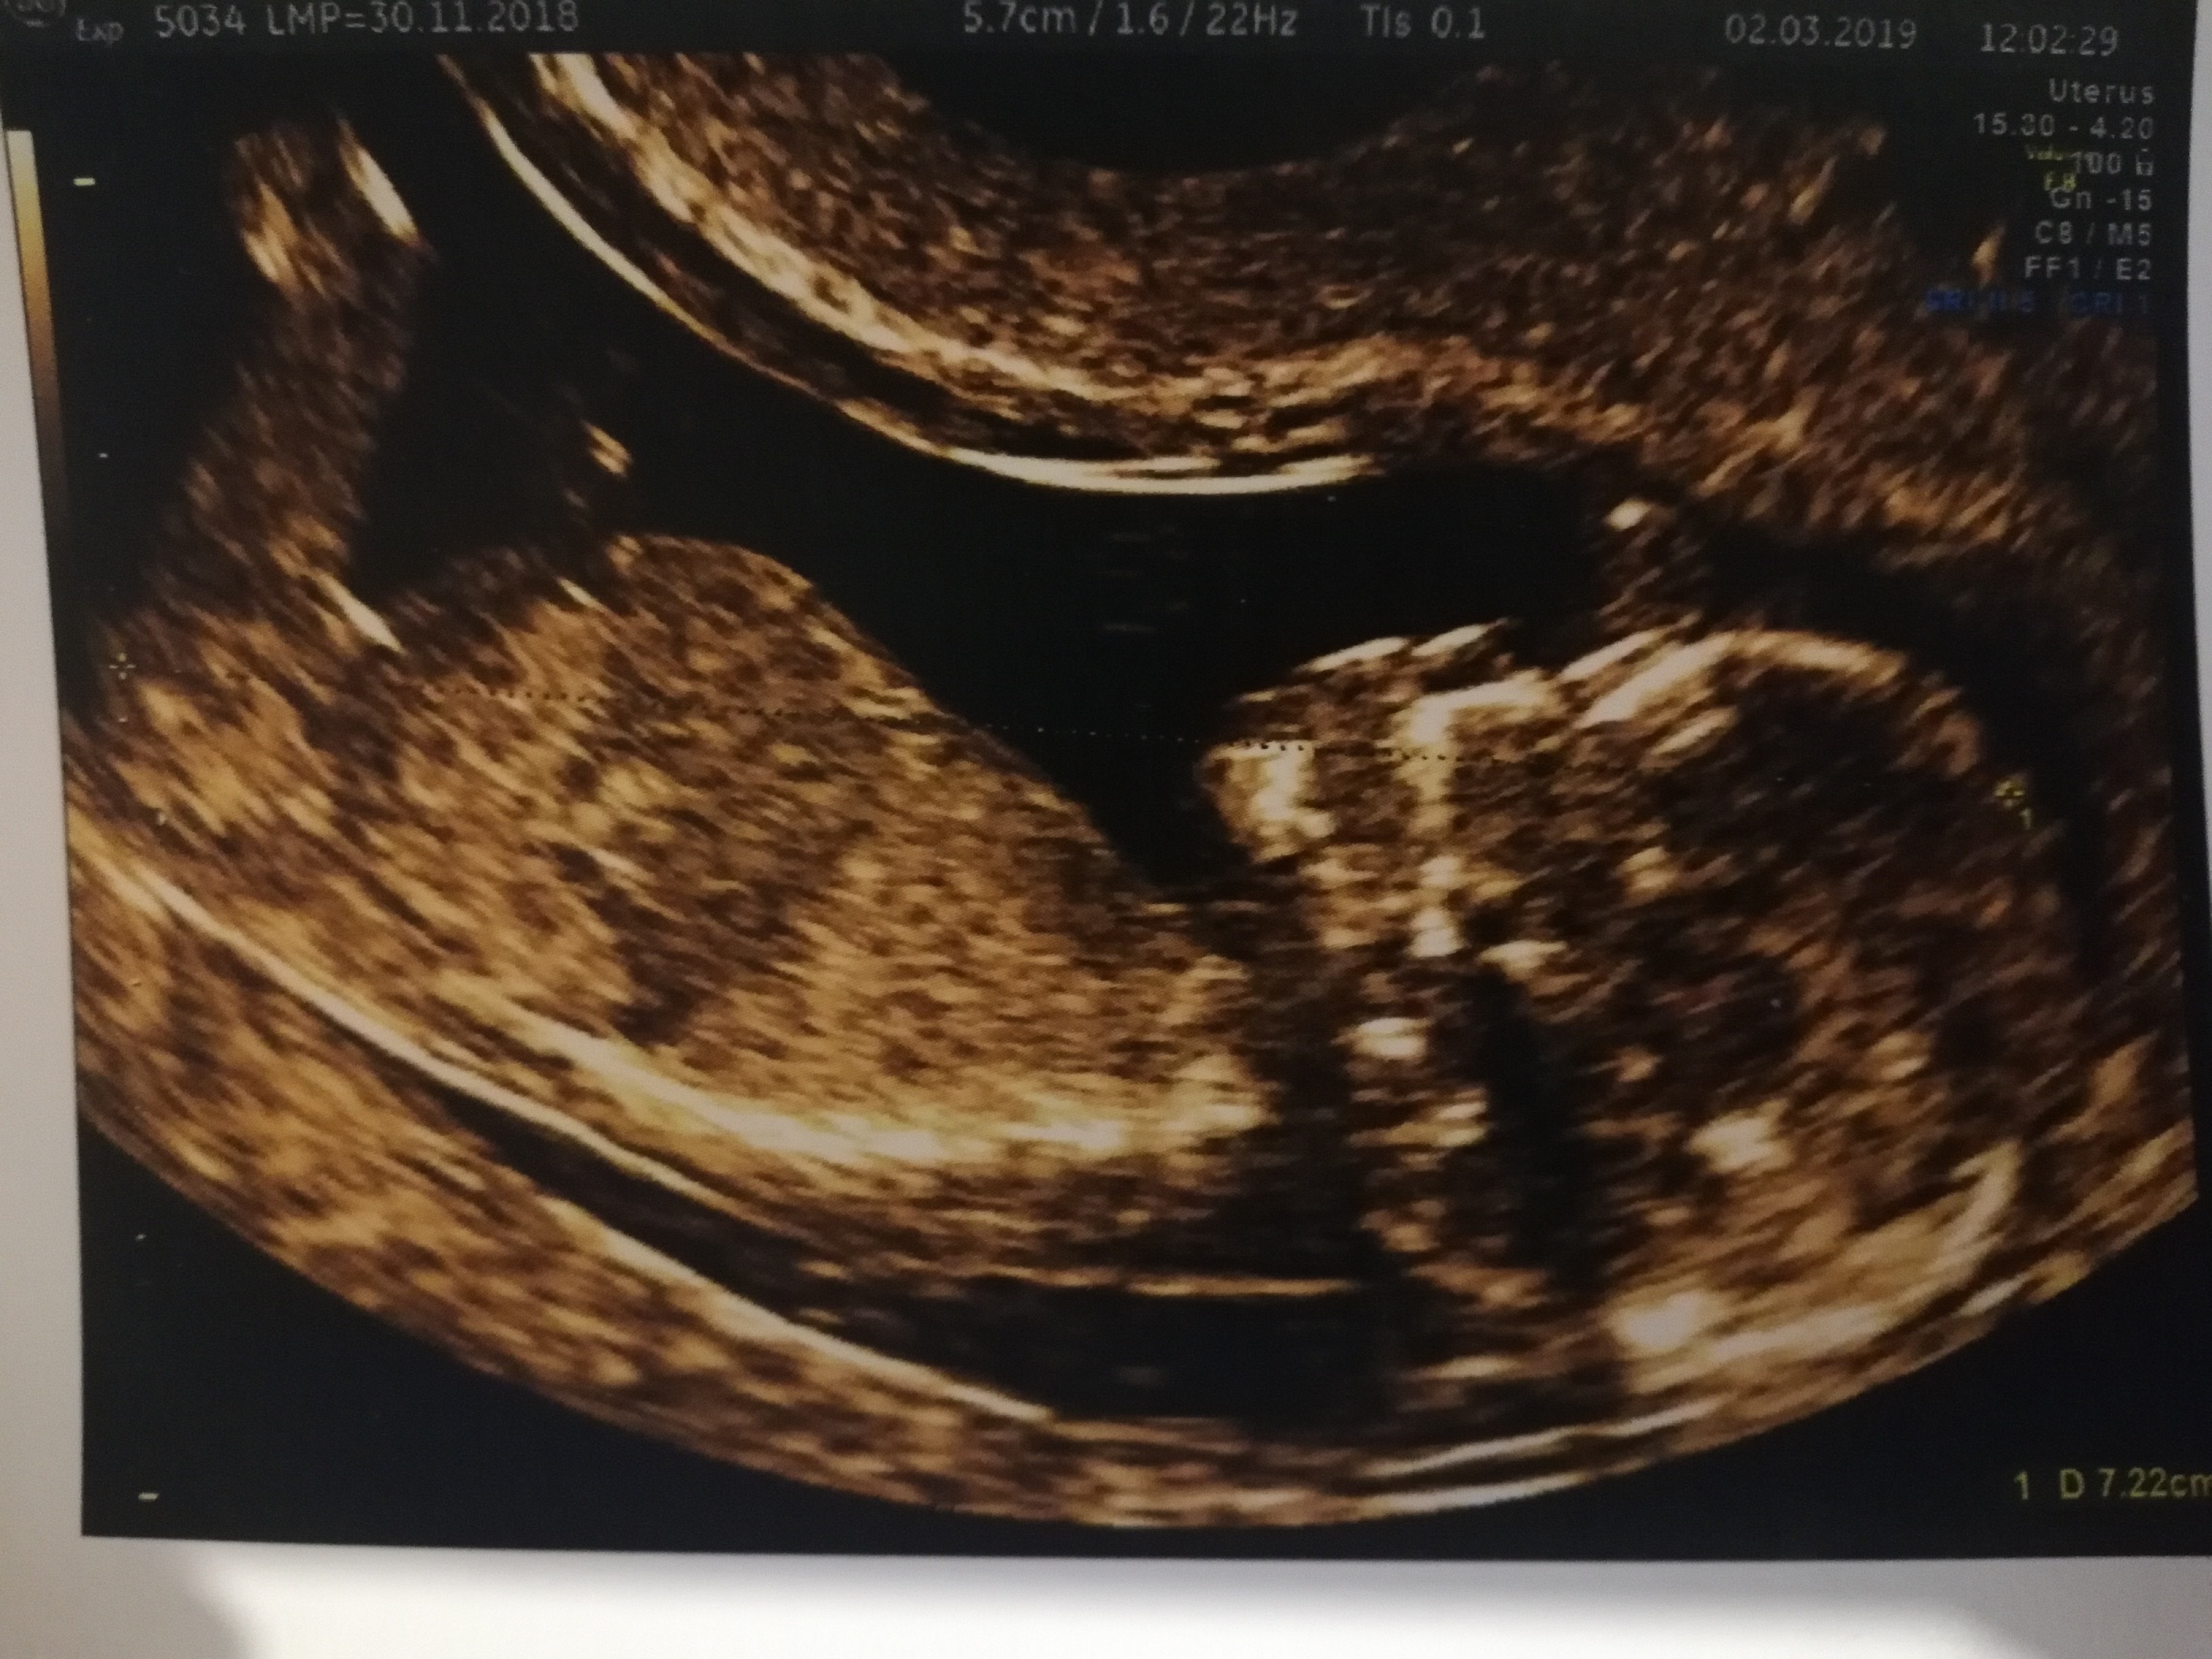

Nasze USG

Mój człowieczek malutki [emoji3590] niecałe 3cm, tętno 171. No kocham go/ją już [emoji28]

Niestety nie. Wstydnis bardzo utrudnial wszystkie pomiary. Musieliśmy zrobić przerwę w badaniu i po pół godziny drugie podejście bo nie mógł lekarz uchwycić ani przeziernosci karkowej, ani kości nosowej nie było widać, ale w końcu się udało. A nóżki zacisniete całe badanie :)